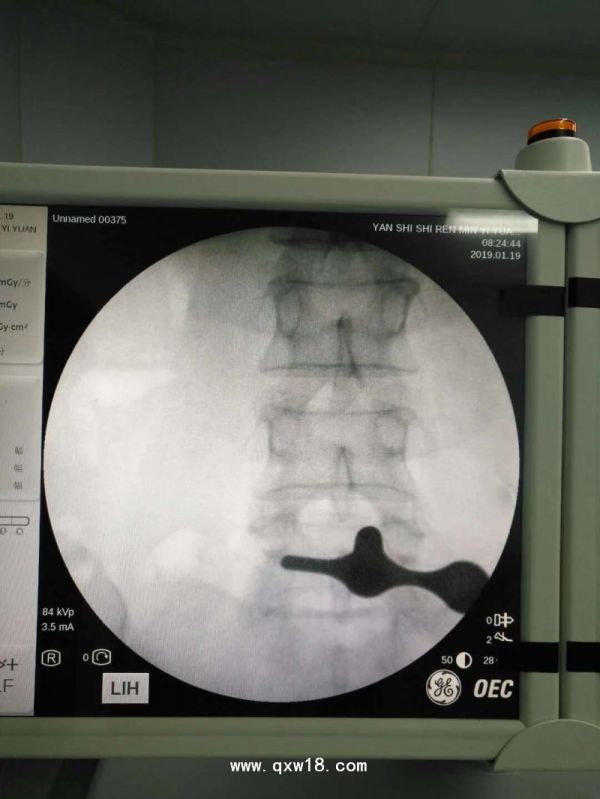

椎间孔镜手术优势一:镜下准确摘除突出髓核。

椎间孔镜手术优势四:目标直接,目前椎间孔镜手术被越来越多的专家认为是治疗椎间盘突出的黄金标准。

椎间孔镜手术优势五:患者创伤痛苦小、适应症广、远期疗效好、操作灵活.易学易用。能处理儿乎所有类型椎间盘突出,区分椎管狭窄、椎间孔狭窄、钙化等骨性病变。

椎间孔镜手术优势六:安全性高、手术风险小,局麻麻醉,术中能与病人互动,不伤及神经和血管;基本不出血,手术视野清晰,大大降低失误操作的风险